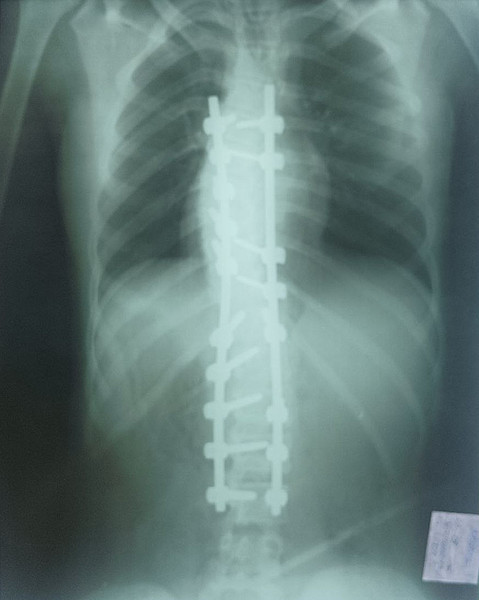

< < <19102022-30photo_2025-08-23_12-17-55До_ОперацияПосле

После.